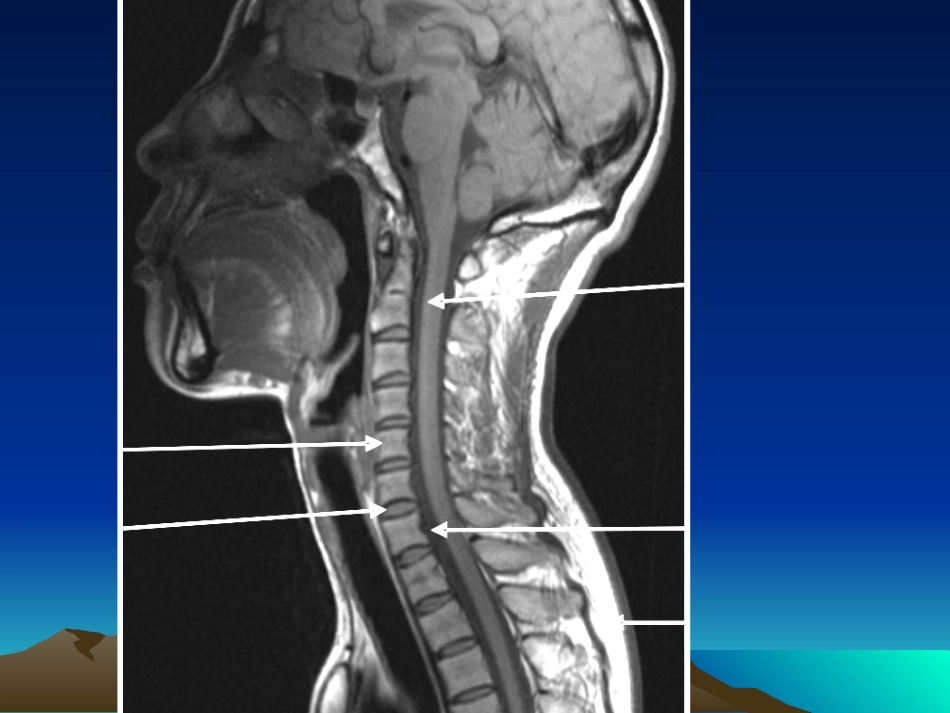

第六节脊髓和椎管内疾病第六节脊髓和椎管内疾病MRMR诊断诊断正常脊柱的扫描系列及表现正常脊柱的扫描系列及表现•Sag-T1WI,矢状位T1加权序列具有成像速度快,定位简单的优势。在该序列上,骨皮质、韧带、蛛网膜下腔呈低信号,骨髓呈中等偏高信号,椎间盘呈中等信号,信号强度低于椎体,脂肪呈高信号,肌纤维间隙因为脂肪的存在而呈高信号,本序列在正常解剖显示上有优势。•Sag-T2WI,矢状位T2加权序列上,骨皮质、韧带呈低信号,骨髓呈中等偏高信号,椎间盘(髓核及内纤维环的信号较外纤维环高)呈中等信号,信号强度高于椎体,蛛网膜下腔、脂肪呈高信号,本序列对于椎间盘、脊髓病变的显示很大的有优势,是临床最常用的序列。Ax-T2WI,轴位T2加权序列上。本序列在椎间盘病变及椎管内占位病变定位上有很大的优势。STIR(FsT2WI)脂肪抑制T2加权,主要用于观察椎体病变•椎管内肿瘤的分类•髓内肿瘤室管膜瘤星形细胞瘤•髓外硬膜内肿瘤神经鞘瘤脊膜瘤•硬膜外肿瘤转移瘤淋巴瘤脊柱和椎管内肿脊柱和椎管内肿瘤瘤•髓内肿瘤定位:脊髓增粗,蛛网膜下腔变窄。•室管膜瘤、星形细胞瘤、血管母细胞瘤一室管膜瘤MR诊断(一)概述室管膜瘤为最常见的髓内肿瘤,占髓内肿瘤的55~65%,常见于20~60岁,男性居多。起病缓慢,疼痛为最常见的首发症状,逐渐出现肿瘤以上节段的运动障碍和感觉异常,表现为肢体无力,肌肉萎缩甚至截瘫等。一室管膜瘤MR诊断(一)概述病理:室管膜瘤发生于脊髓中央以及脊髓终丝的室管膜细胞,可发生于脊髓各段,以脊髓两端为多,好发部位是腰骶段、脊髓圆锥和终丝。绝大多数为良性,仅少部分为恶性,呈膨胀性生长造成对邻近脊髓组织的压迫,骶尾部肿瘤可沿终丝进入神经孔向髓外和硬膜外生长,而此处已无脊髓组织,故有时判断肿瘤位于髓内或髓外十分困难。•组织学上可分为乳头型、粘液乳头型、上皮型、多细胞型和混合型等。其中终丝室管膜瘤以粘液乳头型多见,而颈髓室管膜瘤多为多细胞型。镜下可见瘤内间质少,血管为其主要支架,有时可见血管内皮细胞增生,增生的细胞可将血管堵塞,引起部分瘤组织变性。•室管膜瘤的血供极为丰富,容易出血,出血灶多位于肿瘤边缘,易引起蛛网膜下腔出血。钙化非常少见。•发生种植转移及脊髓空洞形成是室管膜瘤较具特征性的改变,约45%患者伴有继发的脊髓空洞。一室管膜瘤MR诊断(二)MRI诊断1室管膜瘤可发生于脊髓任何部位,且累及几个节段2室管膜瘤常由实性和囊性部分组成3实性部分在T1WI上呈低信号,在T2WI上呈较高信号。4肿瘤周围常有水肿,平扫所见异常信号大于肿瘤实际大小5增强扫描肿瘤实性部分有明显强化6囊性部分由肿瘤坏死液化和脊髓继发性空洞两部分组成,脊髓继发空洞则表现为CSF样信号强度。与星形细胞瘤的鉴别与星形细胞瘤的鉴别•室管膜瘤多位于圆锥部及马尾神经,而星形细胞瘤多位于颈胸段。•室管膜瘤多位于脊髓中央,呈膨胀性生长,而星形细胞瘤则多呈偏心性生长,边界不清楚。•室管膜瘤合并出血的比率高于星形细胞瘤。二星形细胞瘤MR诊断(一)概述星形细胞瘤占髓内肿瘤的25%,常发生在20~50岁之间,男性稍多。发病部位以胸颈段最多(占75%),肿瘤往往累及多个脊髓节段,甚至可累及脊髓全长。病理:肿瘤起于脊髓星形细胞,呈膨胀性或浸润性生长,与正常脊髓无明显分解,肿瘤可发生囊变形成空洞(占38%),空洞可向上延伸至延髓。脊髓星形细胞瘤恶性程度低于脑内,76%为Ⅰ~Ⅱ级,但其恶性程度与肿瘤范围不成比例。二星形细胞瘤MR诊断(二)MRI诊断脊髓呈梭形增粗,肿瘤由实性和囊性部分构成两端脊髓内常并发脊髓空洞在T1WI上病变区呈等或低信号,在T2WI上呈高信号,肿瘤内常出现较小、多发、偏中心分布的囊变区信号不均匀,呈T1WI更低信号和T2WI更高信号。增强扫描肿瘤呈结节状不均匀强化,并有延迟增强现象,有时可呈连续性多个节段增强颈段脊髓内星形细胞瘤颈段脊髓内星形细胞瘤颈段脊髓内星形细胞瘤颈段脊髓内星形细胞瘤颈段脊髓内星形细胞瘤颈段脊髓内星形细胞瘤----增强扫描增强扫描颈段脊髓内星形细胞瘤颈段脊髓内星形细胞瘤----增强扫增强扫描描血管母细胞瘤血管母细胞瘤•占髓内肿瘤的1%~5%....